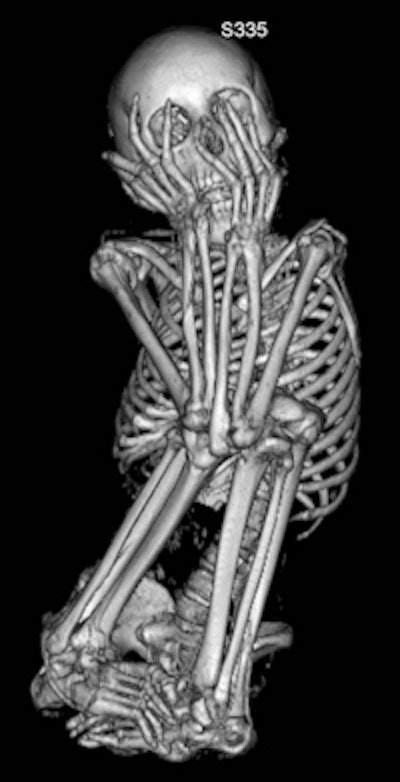

![]() |

| This image, also of the 13-year-old female mummy, shows another view of the typical fetal position body placement. |

Sex and age of the mummies were determined by analyzing body structures such as the pelvis and skull, the authors wrote. Eight mummies were identified as female, three as male, and sex could not be determined for one. The ages of the mummies were newborn, 0.7 years, 2.5 years, 13 years, 13 years, and 16 years, with six mummies identified as being between 20 and 40 years old.

The height of the mummies, estimated by measuring femur and tibia length, ranged from 41 ± 3 cm (newborn) to 145 ± 14 cm (adult).